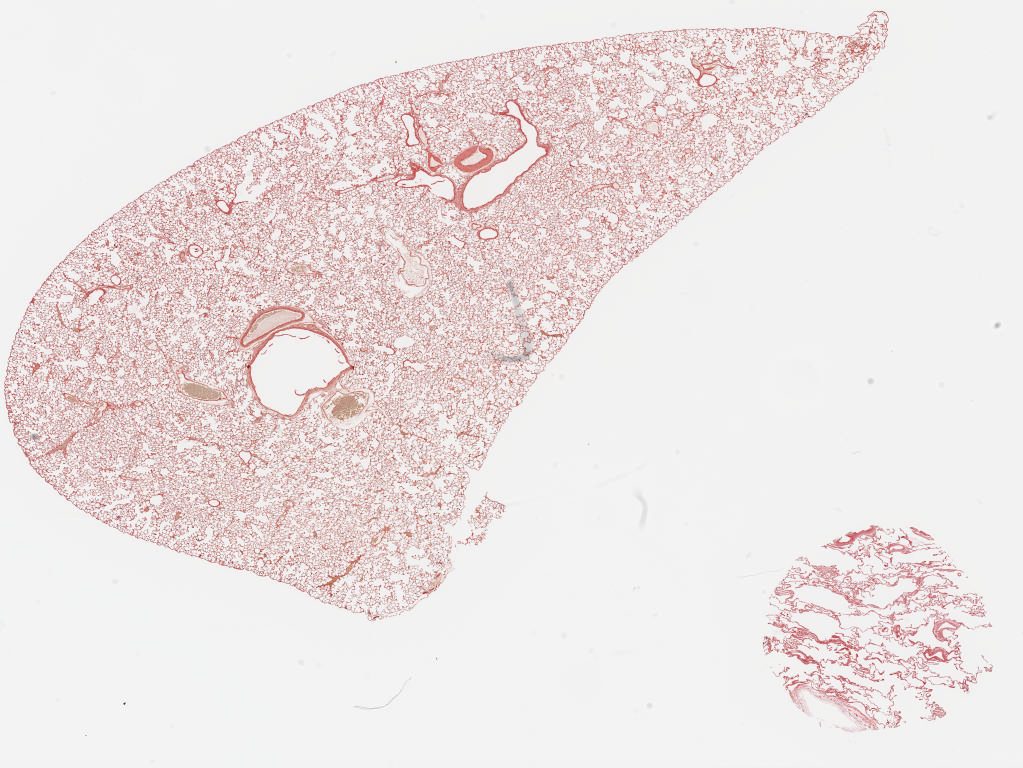

J - PAS Liver.svs

20943 x 22509

@ 40X